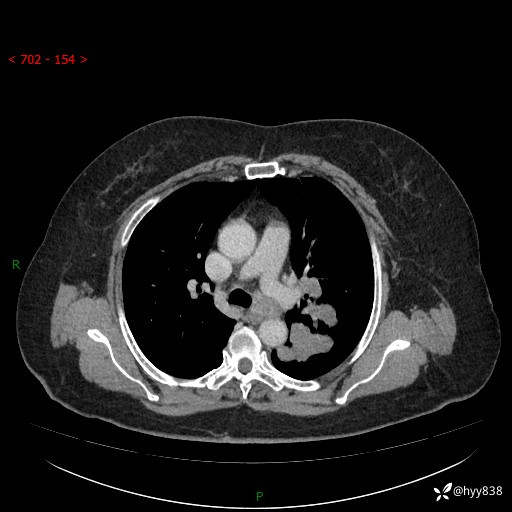

老年女性,左上肺结节8年。典型又不典型,看你如何解读---结果公布(值得分析)

主诉:检查发现左上肺结节8年,较前增大。

简要病史:患者于8年前体检行胸部CT检查发现左上肺结节(4mm),患者平素间断咳嗽咳痰,无心慌、胸闷、胸痛、呼吸困难、低热、盗汗,无头痛、头晕,无腹痛、腹胀等不适,未行特殊处理,定期复查。2023-09-21胸部CT示左上肺结节(2cm)较前增大,2024-02-01胸部CT示左上肺尖后段(39*32mm),左侧肺门及纵隔淋巴结增大,现患者欲求手术治疗,遂来我院就诊,以“左上肺结节”收入我科。 患者自起病以来,精神可,睡眠可,饮食可,大小便正常,体重无明显改变。

辅助检查:CT

胸部CT平扫

增强(动脉期+静脉期)